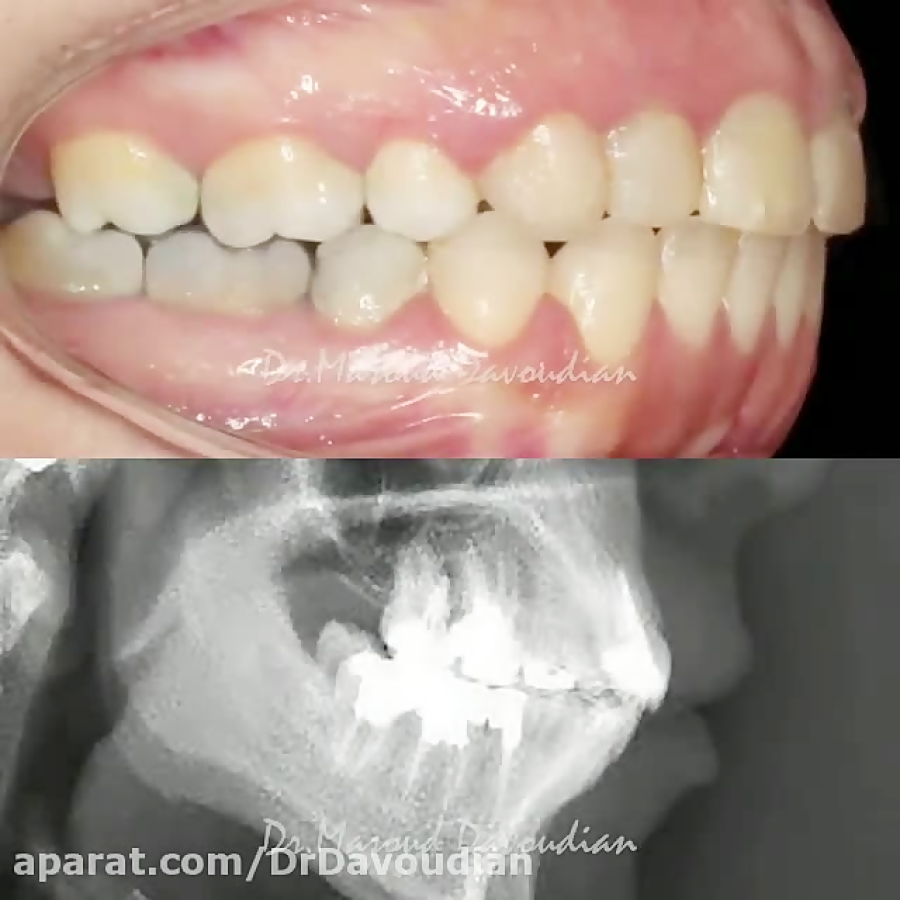

ارتودنسی کراس بایت | دکتر داودیان

ارتودنسی جلو بودن فک بدون جراحی | دکتر داودیان

ارتودنسی نیش نهفته | دکتر داودیان

ارتودنسی اپن بایت بدون جراحی فک | دکتر داودیان

ارتودنسی دیمون بدون کشیدن دندان | دکتر داودیان

ارتودنسی بدون جراحی فک | دکتر داودیان

ارتودنسی عقب بودن فک پایین | دکتر داودیان